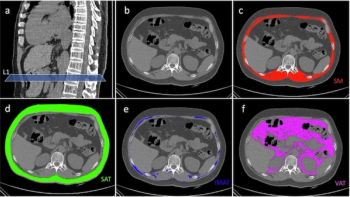

A high intermuscular adipose index has a 49 percent increased likelihood of being associated with lower overall survival in patients with resectable non-small cell lung cancer (NSCLC), according to new research.

For those without low skeletal muscle mass on CT and myosteatosis, obese patients have a 23 percent lower risk of death than non-obese patients after undergoing curative resection for non-small cell lung cancer, according to newly published research.